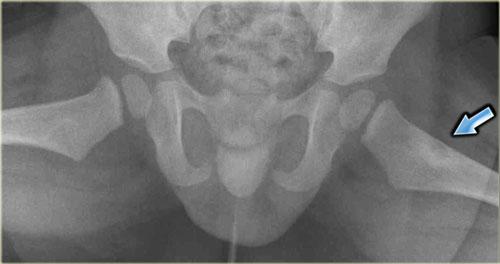

Đây là hình chụp X-quang vùng chậu với một ổ di căn tạo xương hầu như không nhìn thấy ở xương chậu trái (mũi tên xanh lam).

Lưu ý rằng CT mô tả các tổn thương này rõ hơn nhiều (mũi tên đỏ).